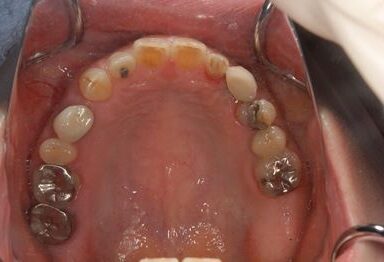

インプラントの症例写真 IMPLANT

インプラント治療

| 主訴 | 乳歯がぐらついている。 | ||||||||||||||||||||||||||||||||

| 治療方針 | インプラント治療にて、機能的・審美的回復を行う。 | ||||||||||||||||||||||||||||||||

| 治療内容 | インプラント1本、メタルボンドセラミッククラウン1本 | ||||||||||||||||||||||||||||||||

| 総治療費 | 377,055円 | ||||||||||||||||||||||||||||||||

| 治療期間 | 4ヶ月 |